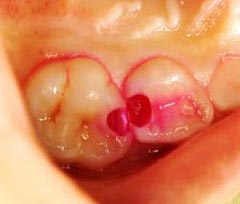

う蝕検知液とは、虫歯の部分のみを赤く染める薬剤です。

虫歯治療を行う上で一番大切なのは、虫歯に感染した部分をしっかり除去することですが、通常は虫歯の硬さを頼りに、軟らかくなった部分を削っていきます。

しかし、この方法では、感染部位を正確に除去することはできません。

そのため、虫歯を確実に取り除くことが出来ないだけでなく、健康な歯まで削ってしまうこともあります。

しかし、このう蝕検知液を使うことで、感染した部分が赤く染まりますので、どこまで虫歯を削ればよいかがわかり、歯を削る量を最小限に抑えることができます。